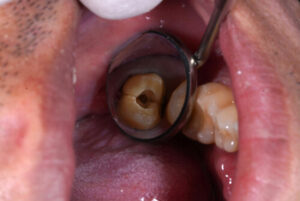

診断の難しさと亀裂の見極め

従来のレントゲン撮影だけでは、歯の根のひび割れを正確に判断することは非常に困難です。

炎症が起きていても、それが「完全な破折」によるものか、「修復可能な亀裂(クラック)」によるものかを判断することはできません。

マイクロスコープ(歯科用顕微鏡)

高倍率の拡大視野で、歯の根の溝(亀裂が入っている可能性のある部分)を詳細に観察し、破折か亀裂かを肉眼レベルで確認します。

亀裂の場合は、その深さや広がりを評価し、修復の可能性を探ります。